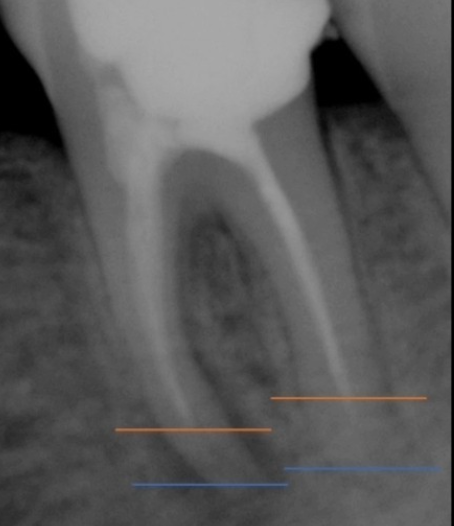

2. 근관확대 : 근관의 신경을 깨끗하게 제거하는 과정으로 신경관의 길이를 측정하게 됩니다.

4. 가압근충 : 비어있는 근관 내부를 치과재료로 채워주는 신경치료의 마지막 과정.

치아마다 모양이 다르고 그 안에 있는 시경은 더욱 복잡하게 얽혀 있어요. 신경관이 막혀 신경을 제거하지 못한 경우도 있고 신경치료를 하였으나 신경조직이 남아있는 경우도 있어요. 치아 상태에 따라 재 신경치료 or 치아 재식술을 통해 치아의 기능을 회복할 수 있어요.

치아 신경치료 후 뿌리 끝에 염증이 생기며 통증이 나타나는 경우도 있어요. 신경치료가 잘 되었음에도 뿌리끝에 염증이 생기는 경우가 있는데요, 이는 복잡한 구조로 제거할 수 없는 근관속 염증이 뿌리끝에 모이게 되면서 잇몸이 부었다 가라앉았다를 반복하는 경우, 통증이 생기는 경우 등의 증상이 생기게 되며 치료방법으로는 치아 재식술 or 임플란트를 통해 치아의 기능을 회복하기도 해요.